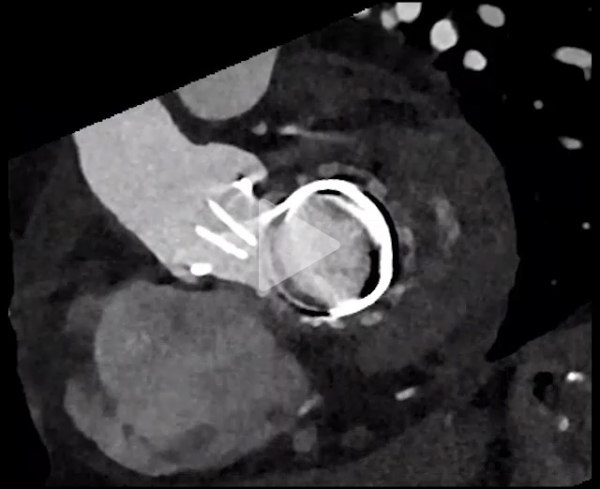

Scanner cardiaque

Vidéo 4

Vidéo 5

Vidéo 6

- Persistance du thrombus (discrète diminution) et blocage de l’ailette

- Absence d'élément de l'appareil sous valvulaire gênant la mobilité

- Bon fonctionnement de la prothèse aortique mécanique